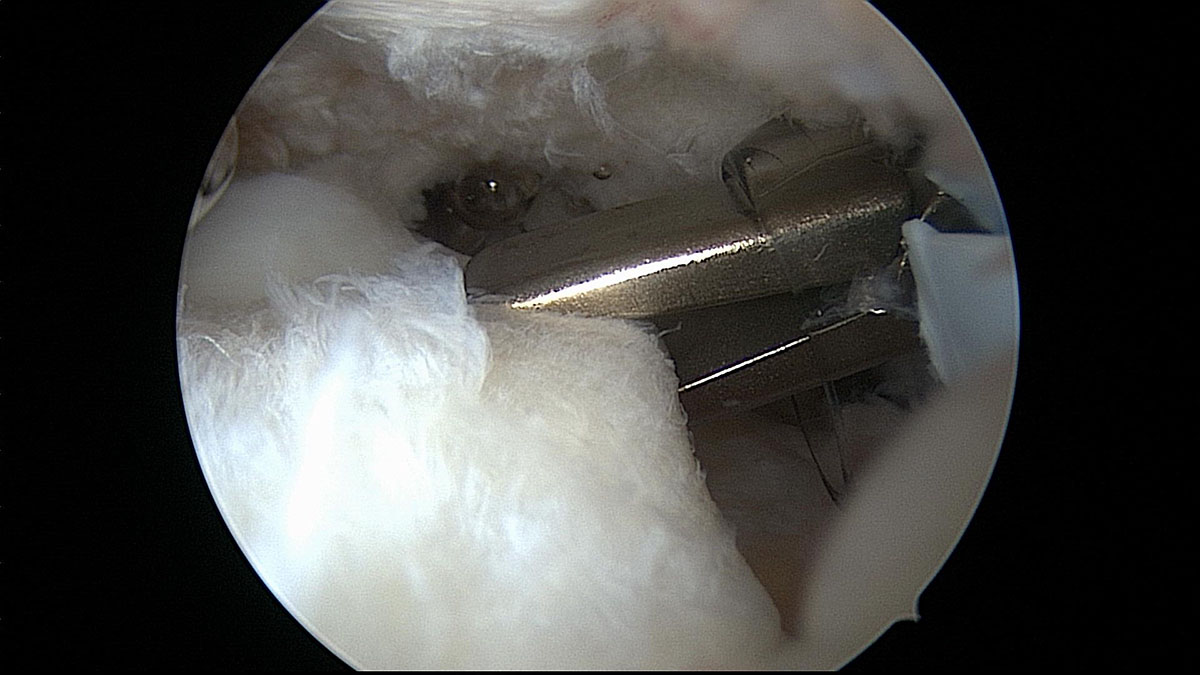

In terms of recovery, you are kind of unique. You may need surgery if you have a weak shoulder joint or ligaments and tend to have recurring shoulder dislocations despite proper strengthening and rehabilitation. Any surgery—even one labeled as “minimally invasive”—is a big deal.

After having a big shoulder surgery, such as a rotator cuff repair, you may not be able to move your shoulder while it heals. Damage inflicted during an mma fight the year before had caused pain for weeks but the patient. You may also need surgery if you have a job in which you.

The procedure itself may only last a few hours or less, but the recovery process can last weeks or months.